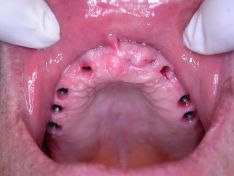

Il paziente è giunto alla mia osservazione con i soli 4 incisivi superiori, i quali presentavano una mobilità di terzo grado. Per questo si è resa necessaria l'estrazione. Il paziente è stato così sottoposto ad un intervento chirurgico implantologico in anestesia locale, in cui sono stati inseriti 7 impianti. Dopo 10 gg. sono state rimosse le suture e si è provveduto ad una protesi totale provvisoria. Dopo 12 settimane dalla chirurgia ho riaperto gli impianti e messo le viti di guarigione per il condizionamento dei tessuti. Attraverso una serie di passaggi, in tre settimane ho posizionato una protesi fissa in ceramica di 12 elementi.

Protesi totale superiore fissa su 7 impianti

Paziente uomo di anni 53 fumatore